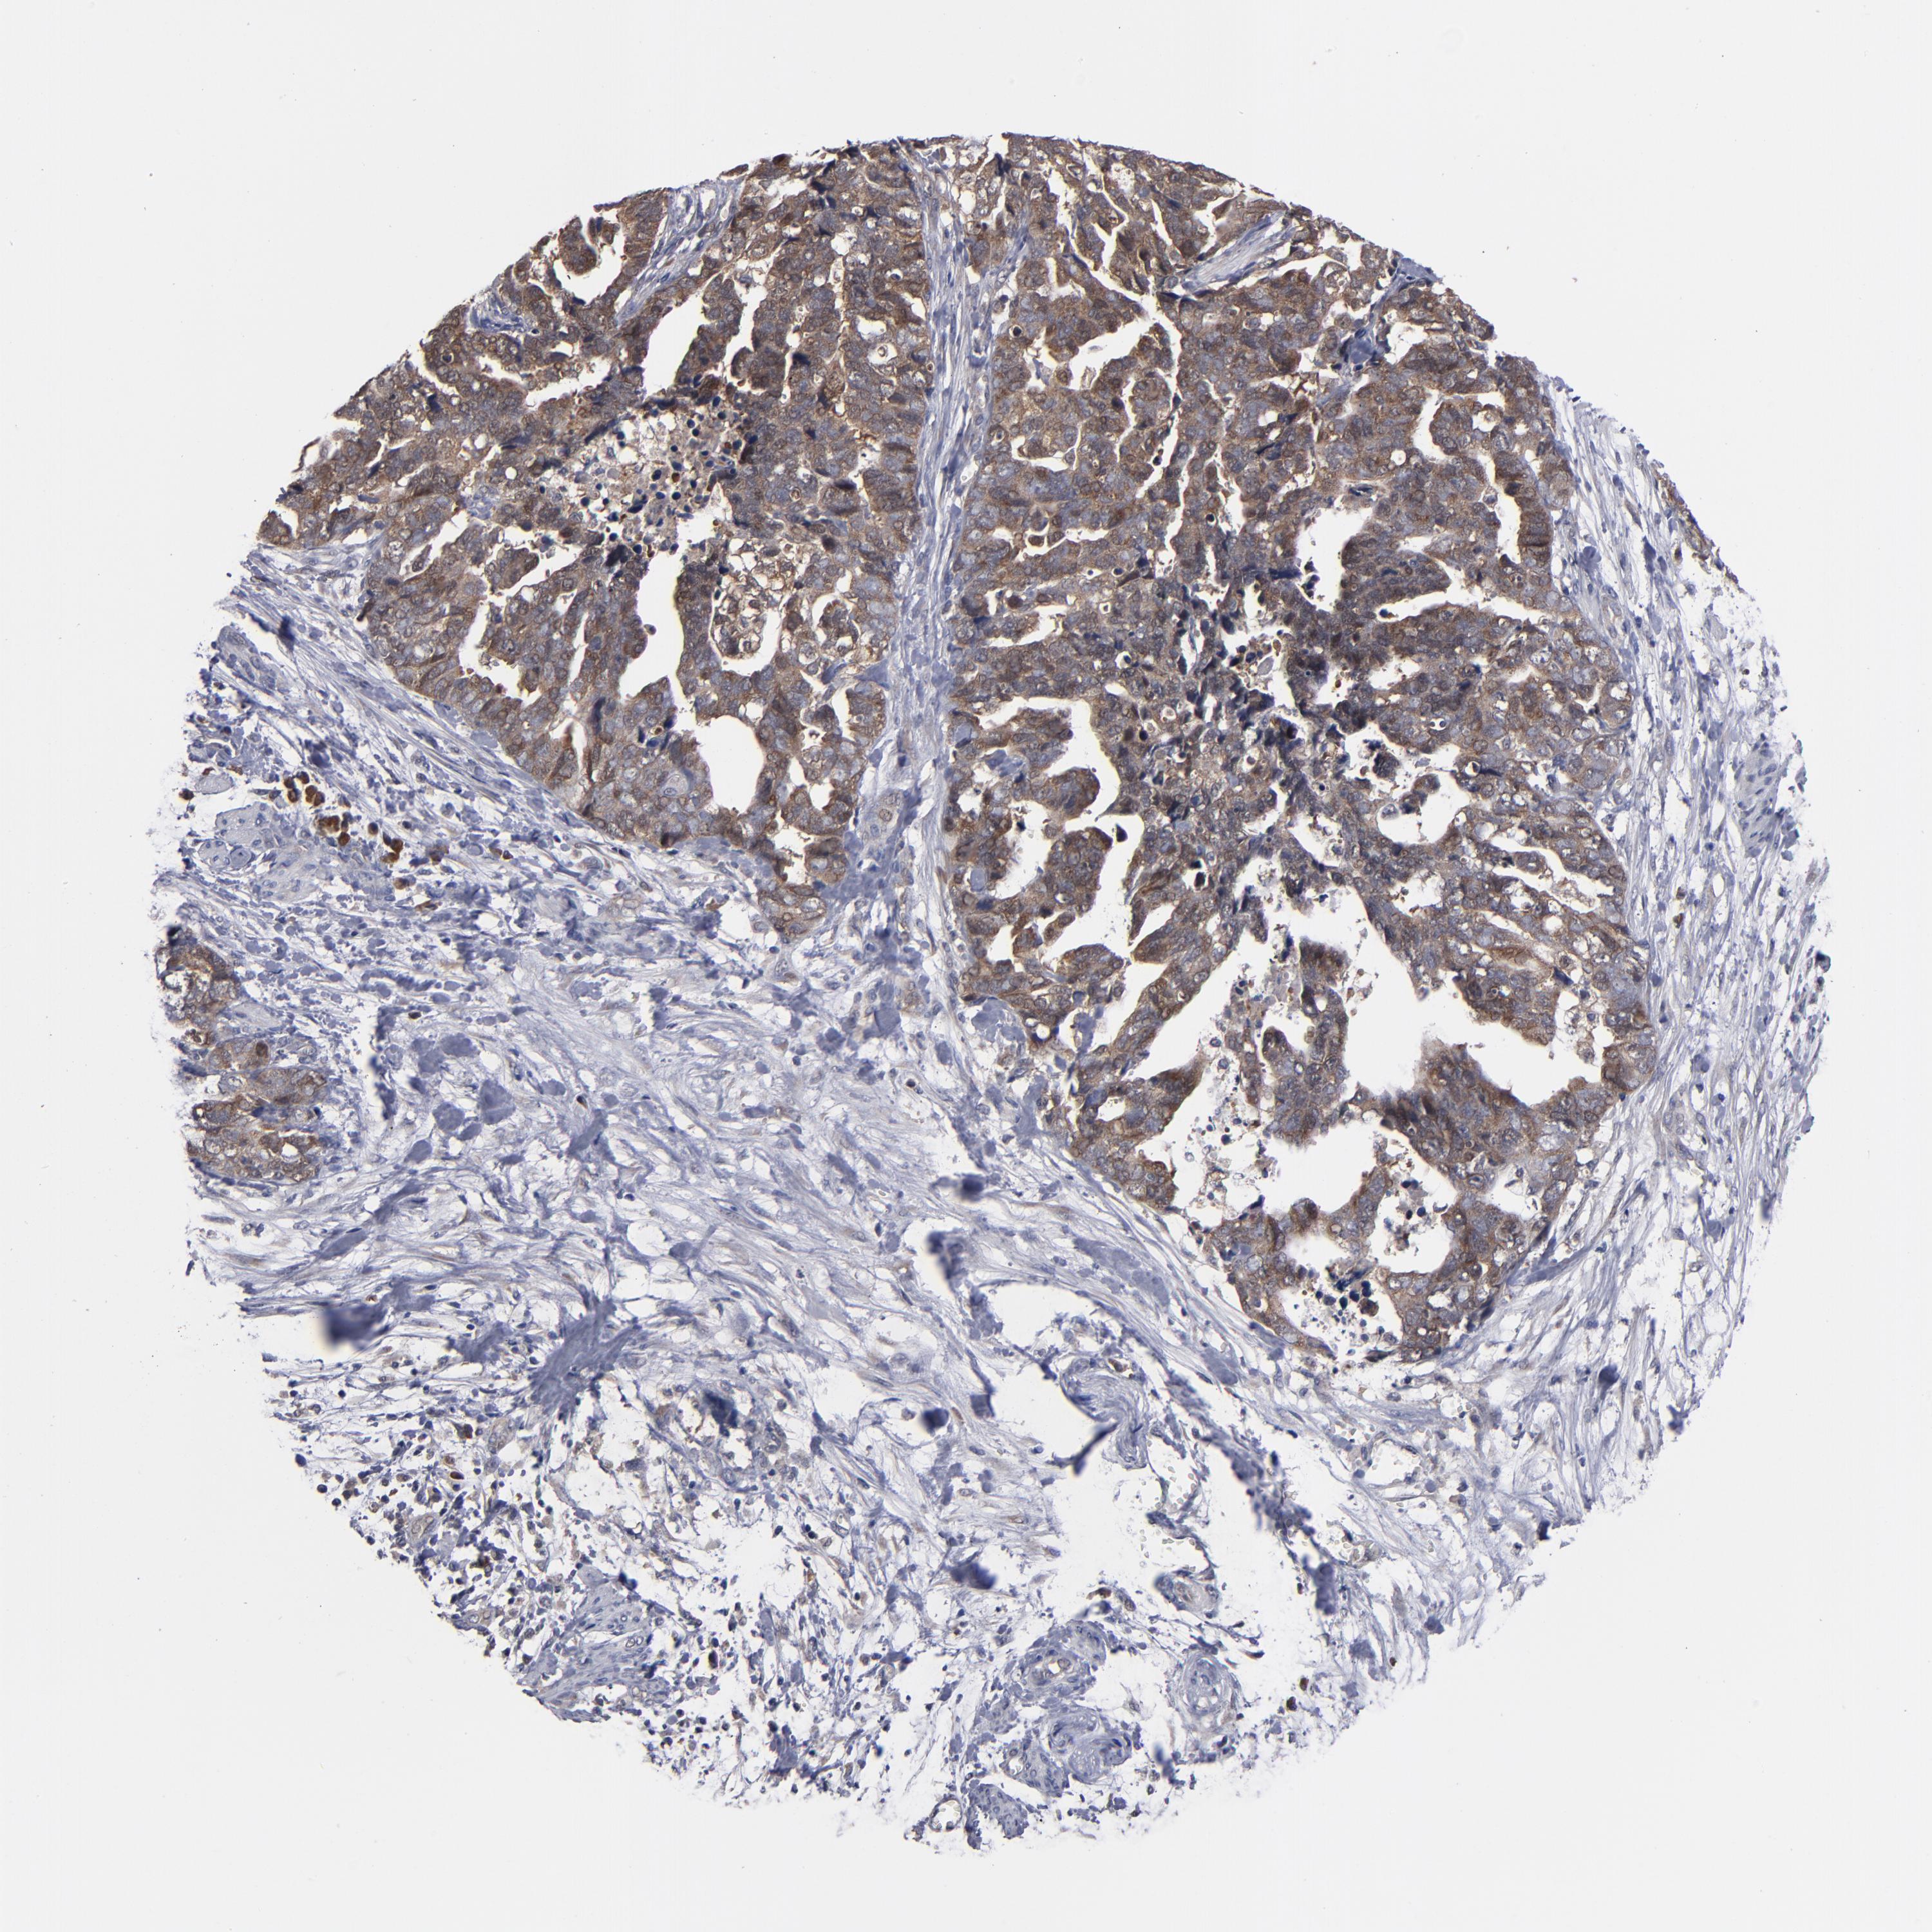

OVARIAN CANCER - Protein expressioni

A mouse-over function shows sample information and annotation data. Click on an image to view it in a full screen mode. Samples can be filtered based on level of antibody staining by selecting one or several of the following categories: high, medium, low and not detected. The assay and annotation is described here.

Note that samples used for immunohistochemistry by the Human Protein Atlas do not correspond to samples in the TCGA dataset.

Antibody stainingi

Antibody staining in the annotated cell types in the current human tissue is reported as not detected, low, medium, or high, based on conventional immunohistochemistry profiling in selected tissues. This score is based on the combination of the staining intensity and fraction of stained cells.

Each image is clickable and will lead to virtual microscopy that enables deeper exploration of all samples and also displays staining intensity scores, fraction scores and subcellular localization as well as patient and tissue information for each sample.

Antibody HPA002853

Staining

High

Medium

Low

Not detected

Intensity

Strong

Moderate

Weak

Negative

Quantity

>75%

75%-25%

<25%

None

Location

Nuclear

Cytoplasmic/membranous

Cytoplasmic/membranous,nuclear

Cystadenocarcinoma, serous, NOS

Cystadenocarcinoma, mucinous, NOS

Carcinoma, endometroid